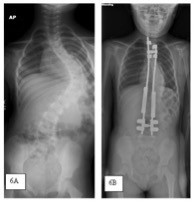

Ain’t no one getting spine lengthening that’s just paralysis speed runThe scoliosis disc replacement thing has that effect but it’s fucking brutal. I looked at it briefly and then JFL’d.

The scoliosis disc replacement thing has that effect but it’s fucking brutal. I looked at it briefly and then JFL’d.